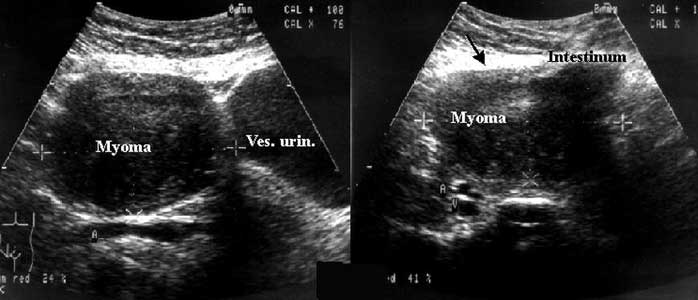

Обычно на фото при УЗИ выявляются увеличенные размеры главного женского органа и возникновение в маточной полости сгустка округлой формы, который, к тому же, хорошо проводит звук. Если матка на фото УЗИ изменила свою форму, значит, миоматозные узлы достигли уже весьма приличных размеров.

Стоит отметить, что миома матки фото на УЗИ будет выглядеть как совершенно иная от матки структура. Размеры ее обычно указываются в неделях беременности, который будет свидетельствовать на самом деле о размере главного женского органа, соответствующего сроку вынашивания ребенка.

Фото 1. Как выглядит миома матки на УЗИ.

Врач-сонолог определяет миому как округлый объект с гетерогенной структурой и чёткими границами, делающими сигнал датчика слабее.

Эхогенность и структурные особенности миомы напрямую зависят от места возникновения опухоли и от типа тканей, её образующих. К примеру:

- дейомиомы будут выглядеть на экране УЗ-аппарата как однородные, гипоэхогенные образования (из-за гладкомышечных волокон низкой дифференциации);

- фибромы врачи отмечают как более “светлые” образования повышенной плотности.